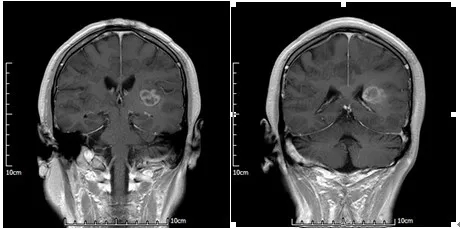

术前TPS计划

山东省医学影像学研究所/磁共振微创介入科的李成利主任在了解满女士的病情后,采取了

磁共振联合个体化平行插植3D打印模板引导I125放射性粒子植入治疗。